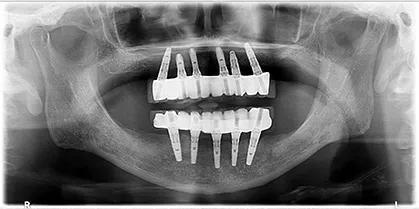

- BEFORE

| 年代・性別 | 70代・男性 |

|---|---|

| 主訴 | 今使っている入れ歯が合わず、嚙むと痛い |

| 治療部位 | 15~26、36、45 |

| 治療内容 | 上下顎インプラント埋入術(上顎5本、下顎2本)を、2回に分けて実施。26部はソケットリフトを適用し、2回法で実施。他部位は1回法。 |

| 金額(税込) | 29,000,000円(税込) |

| 治療期間 | 7カ月(インプラント埋入から上部構造装着まで) 12年経過例(2024年3月時点) |

| リスクと副作用 | 手術部位の腫脹、疼痛 マスダ歯科のインプラント詳細はこちら |